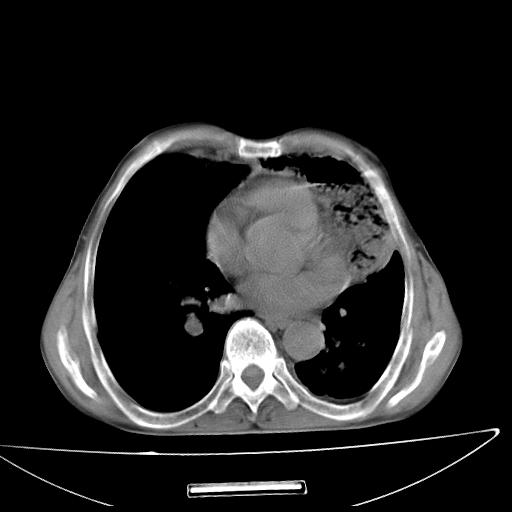

男  70岁,发烧咳嗽4天。盗汗,消瘦。无痰中带血丝,以前有肺tb病史,ct见,双肺tb,左侧胸廓塌陷,左胸膜肥厚粘连。纵隔移位,右侧胸腔积液,大家说说那个心影前左肺舌叶除了肺大炮还有炎症还是干酪性肺炎?有占位吗?我看纵隔淋巴结也大。

是胃,纵膈未见明显肿大淋巴结。

1)两肺继发性肺结核并左肺上叶肺不张,支气管扩张。2)双侧胸膜炎(胸膜增厚+少量胸腔积液)。